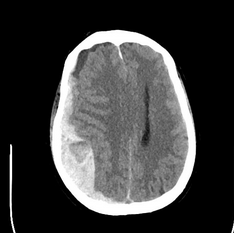

On ICU arrival, the temperature is 37.8°C, heart rate is 89/min, BP is 156/85 mm Hg, and respiratory rate is 25/min without spontaneous respiratory efforts with volume targeted assist-control ventilation. The patient is unresponsive without movement to painful stimuli, with dilated, minimally reactive pupils and no cranial nerve reflexes on rapid neurologic assessment. General examination demonstrates scattered crackles, a palpable spleen, and 1+ bilateral lower extremity edema. The WBC count is 150,500/μL (150.5 × 109/L) with 34% circulating blasts and multiple immature WBC and RBC forms. Laboratory test results are shown in Figure 1. The creatinine level is baseline normal. There is a mildly elevated lactate dehydrogenase level and unconjugated hyperbilirubinemia. Prothrombin and partial thromboplastin times are normal. Representative images of the chest CT scanning performed on admission and head CT scanning performed after intubation are shown (Figure 2 and Figure 3).